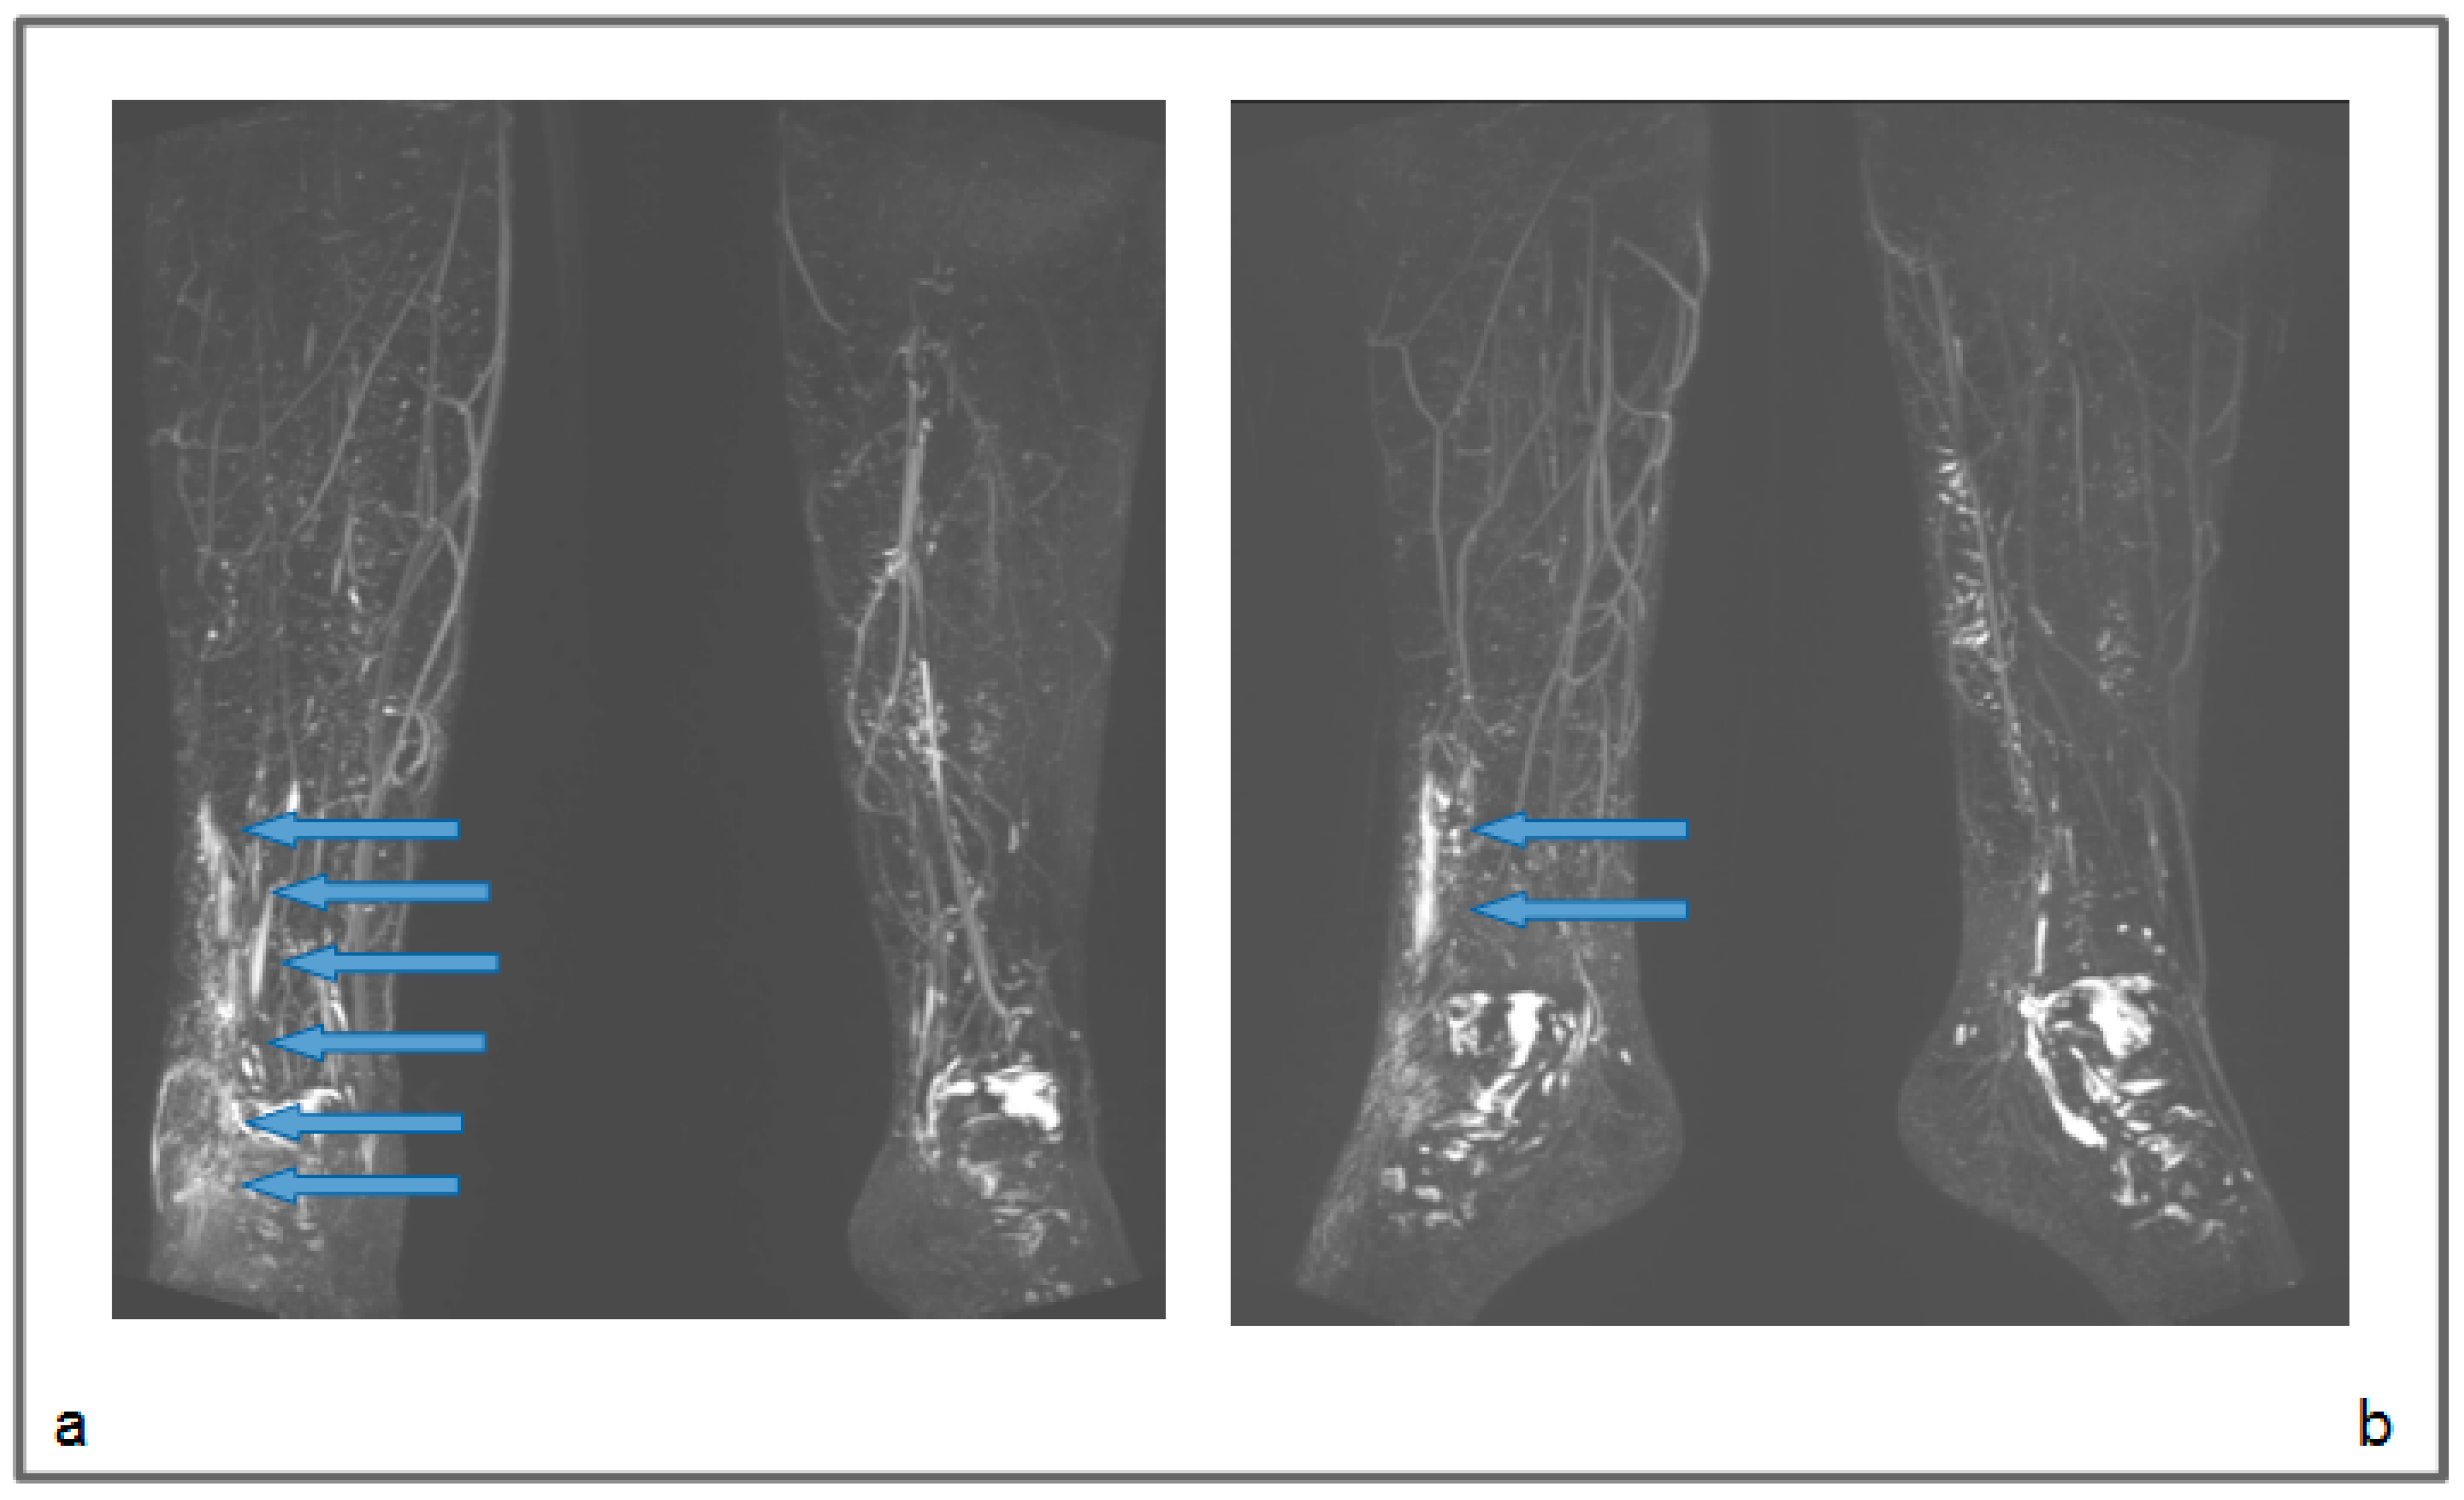

Figure 4.

Patient 1: Preoperative non-contrast MR lymphography (a) and at 1-year follow-up (b). MRI was based on 3D high-spatial-resolution, heavily T2-weighted acquisitions, resulting in a signal loss in the tissue background (like the sequences applied in cholangiopancreatography and MR urography), and enhancement of static fluids like epifascial fluid collections and lymphatic vessels. The follow-up demonstrates the appearance of new inguinal lymphatic vessels (b; blue arrows), that were not visible in the preoperative MR lymphography.

Figure 5.

Patient 2: Preoperative (a) and follow-up (b) non-contrast MR lymphography, 1 year after the surgical procedure, based on high-resolution heavily T2-weighted coronal sequences (turbo spin echo with repetition time 2870 ms, echo time 797 ms, field of view 380 × 380 mm, matrix 358 × 384, slice thickness 1 mm). The follow-up lymphography demonstrates the creation of new inguinal lymphatic vessels (b; blue arrows), that were not visible at the first examination (a).